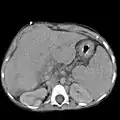

Ultrasound of liver (left side of the image) and right kidney (right side of the image) and Morison's pouch, not containing fluid - Abdominal CT, showing Morison's pouch as the dark margin surrounding the right kidney (at lower left corner of image)